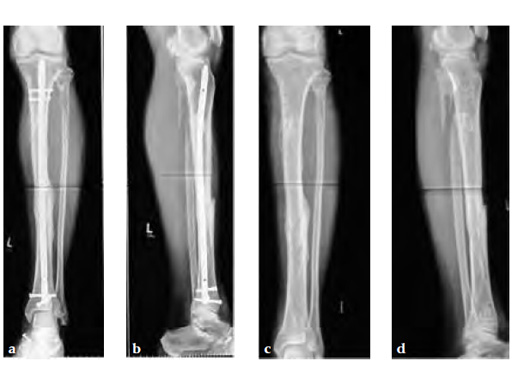

Partial weight bearing started on postoperative day 2 (with 2030kg). The weight was gradually increased over the following weeks. At 6 weeks, the patient was able to fully bear weight even though a high fibula fracture was present and no callus had yet formed. This suggests that angular stable interlocking of the nail markedly enhances stability. The patient was able to bear weight faster than planned and full weight bearing was possible with little pain.

Twelve-week follow-up shows callus formation, and the patient was able to fully bear weight without any pain.

The nail was removed 15 months postinjury as planned. There is good callus formation and proper healing of the tibia fracture.